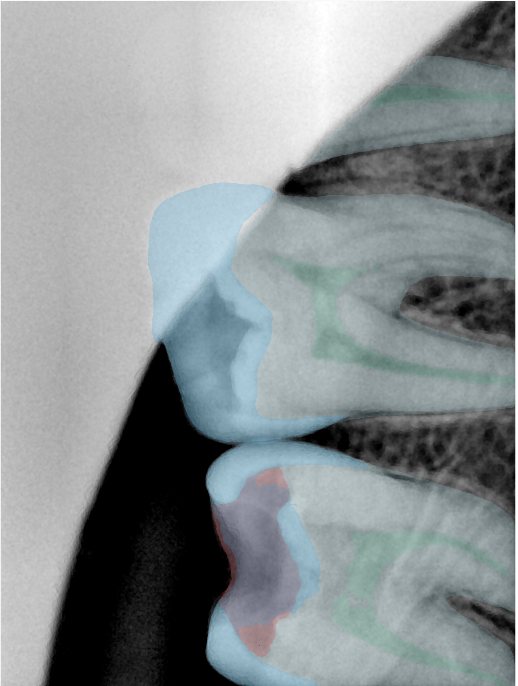

CR/DR 牙齿分割阶段记录

当前进展

- 完成了 CR/DR 牙齿相关分割训练

- 当前结果已经达到阶段预期,但仍有细节问题需要继续处理

相关测试

遇到的问题

- 训练过程中出现过 mask 下移问题

- 部分结果会出现 box 填充异常

- mask 边缘仍然有比较明显的锯齿感

参考

第三版算法分辨率效果比较

Updated: 2026-04-13(更新日期)

| 编号 | 原图 | 第一版 | 第二版 | 第三版 1216x1600 | 第三版 768x1024 | 第三版 1120x1120 |